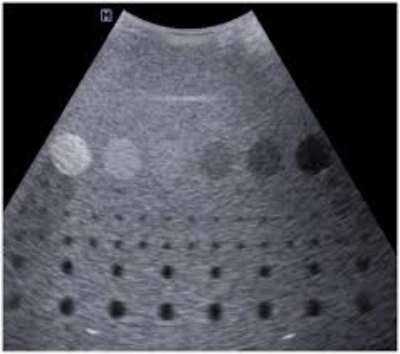

O reparo de transdutor é um serviço técnico essencial para identificar e corrigir possíveis falhas nos sensores utilizados em aparelhos de ultrassom .

Com procedimentos que envolvem inspeções detalhadas, ajustes, substituição de componentes e testes de funcionamento, o reparo promove a precisão necessária para a obtenção de imagens de qualidade.

Ao identificar e corrigir falhas nos sensores, é possível obter imagens mais nítidas e precisas, contribuindo para a segurança e eficácia dos procedimentos médicos.

Em seguida, são realizados testes de funcionamento para assegurar que o transdutor esteja operando corretamente e que as imagens geradas sejam precisas.